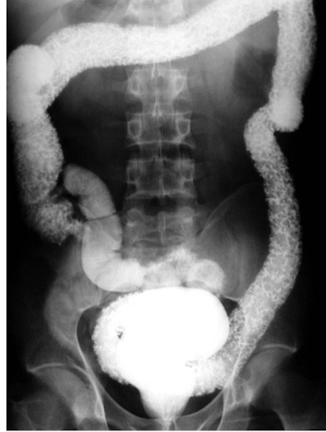

What is this and what type of scan

Crohns, Upper GI w sm bowel follow through